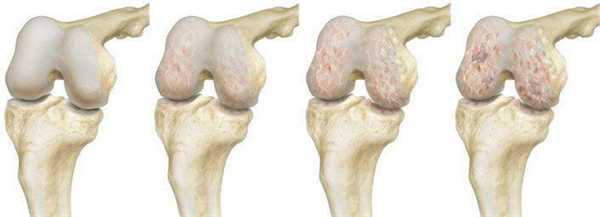

Замена коленного сустава: что это, видео-фото операций, технологии, сроки восстановления

Замена коленного сустава (ЗКС) - метод хирургического лечения последствий дегенеративно-дистрофического патогенеза колена. Цель операции полное восстановление функций проблемного отдела конечности за счет замены необратимо пораженного сочленения эндопротезом. Гонартроз 3-й степени (в 85% случаев) самая частая причина.

Посмотрите на рентген, на нем вы видите, до какой степени при запущенном гонартрозе изношен гиалиновый хрящ, обеспечивающий гладкое скольжение суставных поверхностей. Концевые участки костей грубо деформируются нарушая функции сгибания и разгибания конечности вызывая интенсивный болевой синдром.

Сравнение здорового и пораженного сустава.

Динамика болезни на рентгене.

Динамика разрушения хрящевой поверхности.